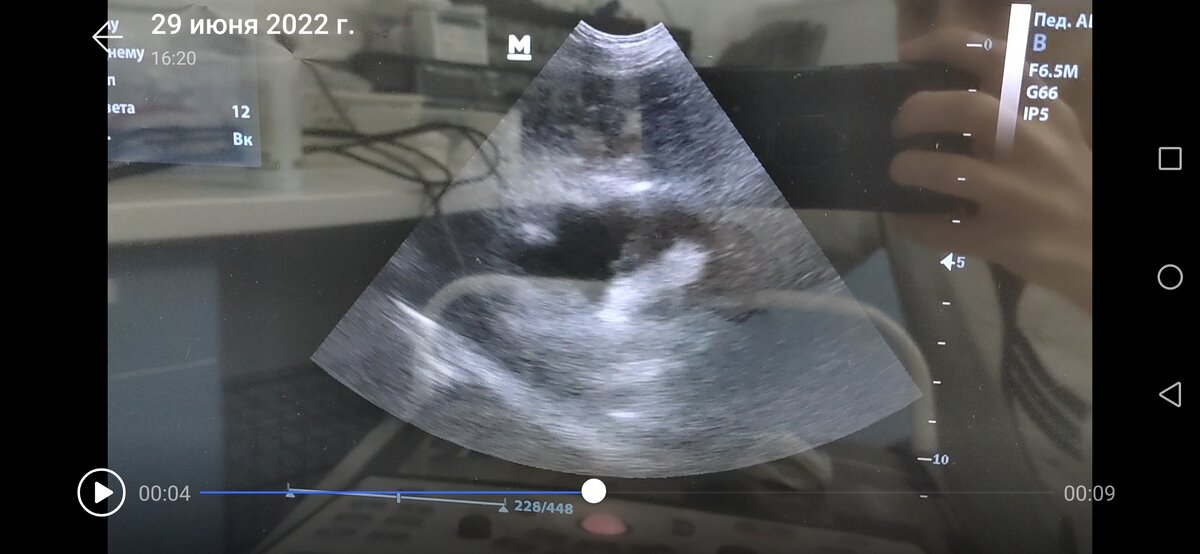

3. Признаки холангиогепатита и холецистита, печень увеличена с диффузным усилением эхогенности, в желчном пузыре неоднородное содержимое, визуализируется гиперэхогенный сладж на дне, который напоминает звездчатую структура, возможно, это начало процесса мукоцеле. Необходим мониторинг данного процесса.